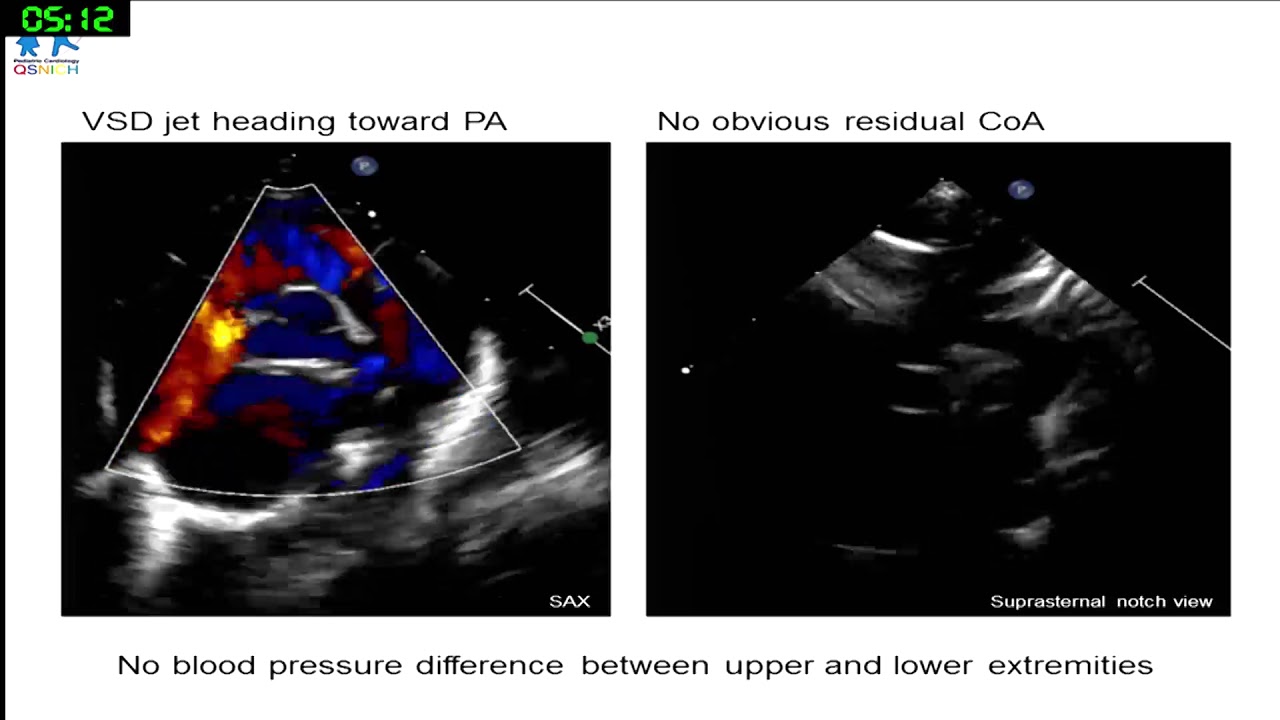

Helping the baby out: device closure for outlet VSD with respiratory failure

Worakan Promphan

(Queen Sirikit National Institute of Child health, Thailand)